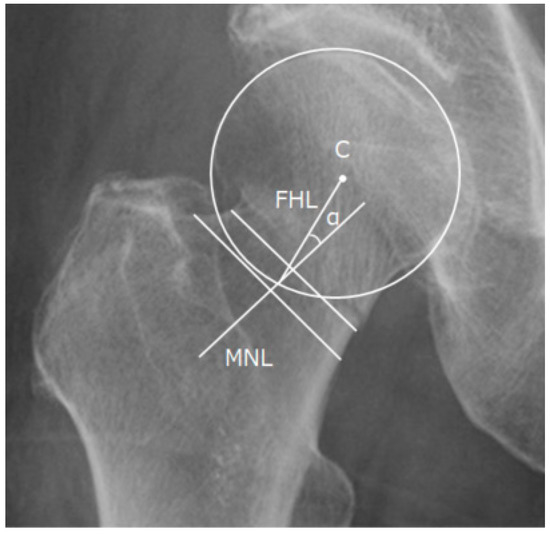

2.4. Radiographic Measurements

2.6. Valgus Tilt Measurement